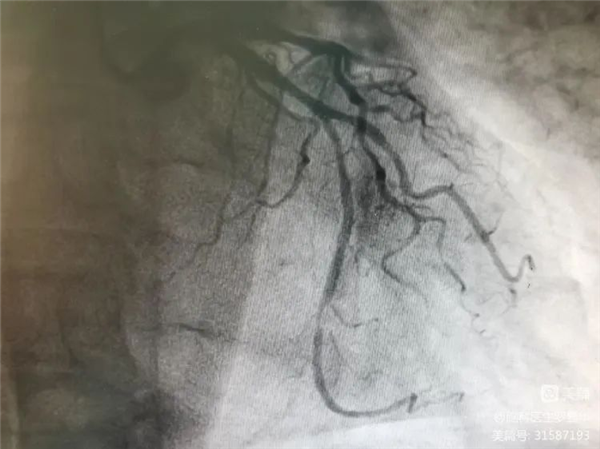

冠脈造影證實(shí)左旋支重度狹窄